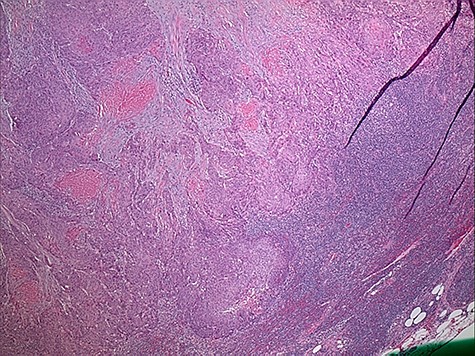

The patient’s post-operative course was complicated by dysphagia requiring gastrostomy tube placement. Surveillance imaging of the chest showed extensive mediastinal, hilar and supraclavicular lymphadenopathy with new pulmonary nodules and a large mediastinal mass encasing the trachea and ascending aorta consistent with distant metastatic disease. Cardiothoracic surgery was consulted and deemed the mass unresectable. On subsequent follow up, the patient endorsed a 2-year history of melena and was referred to gastroenterology for colonoscopy. However, prior to the scheduled colonoscopy, the patient was found to have abdominal distention with imaging confirming colonic pneumatosis and a large mass in the ascending colon. The patient’s clinical condition deteriorated despite non-operative management. He underwent exploratory laparotomy with right hemicolectomy, transverse colectomy and end ileostomy. Pathology workup included concurrent comparison of the salivary gland and colonic tumors, which showed similar histologic features. p63 and CK5/6 immunohistochemistry stain positivity in the colonic tumor confirmed the presence of SCC. CK20 and CDX2 immunostains to exclude a colonic primary adenocarcinoma or adenosquamous carcinoma were negative. In addition, due to the unusual initial presentation of a squamous appearing tumor in the submandibular gland, a MAML2 (11q21) rearrangement FISH study to rule out mucoepidermoid carcinoma (with squamous predominating features) was performed and was negative (Figs 3 and 4).